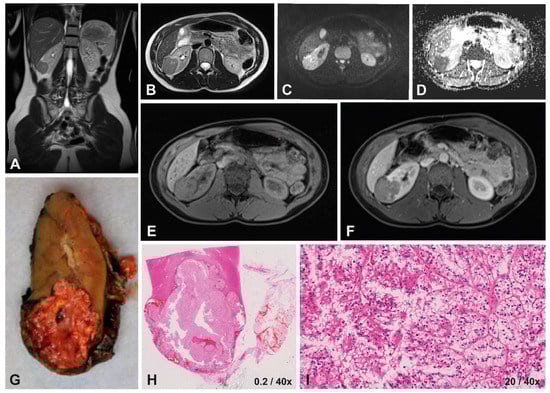

3.1. Case Presentation

3.1.3. Imaging Characteristics at Diagnosis

3.1.4. Diffusion-Weighted Imaging